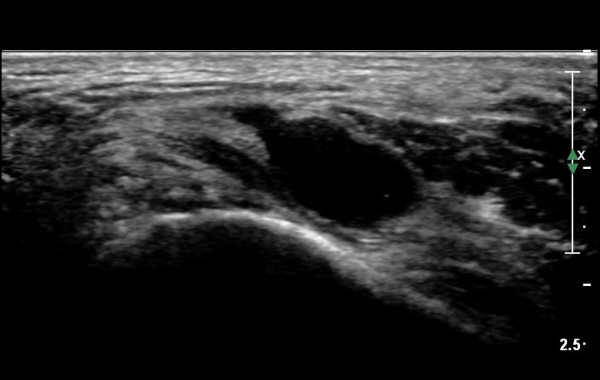

ŽÃËÀÚ¸¦ Á¶±Ý ´õ ¸»´ÜÀ¸·Î À̵¿ÇÏ´Ï Á¶±Ý¸¸ ³¶Á¾ÀÌ µÎ ½Å°æ »çÀÌ¿¡¼­ °üÂûµÈ´Ù(»çÁø 3).